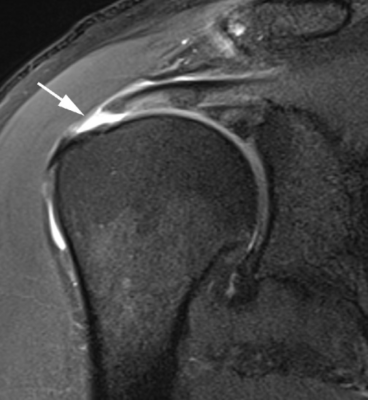

Chụp cộng hưởng từ (MRI):

Dành cho nghi ngờ rách CCX và không cải thiện triệu chứng dù điều trị đầy đủ 3-6 tuần. MRI có thể phát hiện nhiều tổn thương CCX từ thoái hoá đến rách hoàn toàn. MRI là phương pháp chẩn đoán hình ảnh tốt hơn nhiều phương pháp khác, đặc biệt là rách một phần. Nó có thể phát hiện rách trong gân hoặc rách gân mặt bao hoạt dịch, mà những phương pháp khác khó phát hiện. MRI cũng có thể ghi nhận những tổn thương mô mềm khác như cơ, dây chằng, bao khớp, sụn khớp, tuỷ xương.